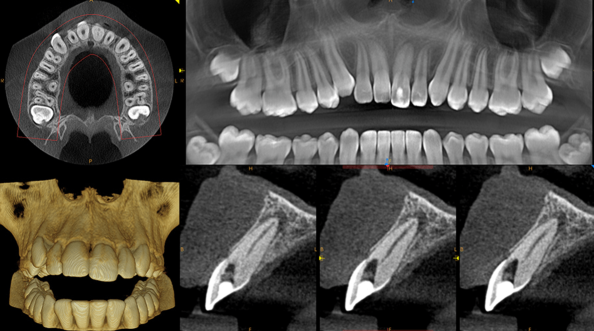

The ultimate in versatility, the CS 9300 system combines dedicated panoramic, optional one-shot cephalometric and up to 7 selectable fields of view cone beam 3D images for the widest range of dental applications.

Panoramic - CS 9300 delivers fast and accurate panoramic images including: standard, pediatric and segmented, TMJ (2 or 4 views) and maxillary sinus. The adjustable focal trough ensures anatomically correct images each and every time.

3D - The innovative CS 9300 delivers crystal-clear, high-quality 3D/CBCT images in seconds. Choose from a variety of fields of view, including Focused, Single/Dual Jaw, TMJ (2x and 4x), Sinus, and Maxillofacial options. The included CS 3D Imaging software enhances treatment planning and facilitates patient communication.

Adjustable Fov - CS 9300 captures a wide range of field of view sizes (5x5, 10x5, 8x8, 10x10 cm) to support a variety of dental applications - from single implants to complete maxillofacial exams.